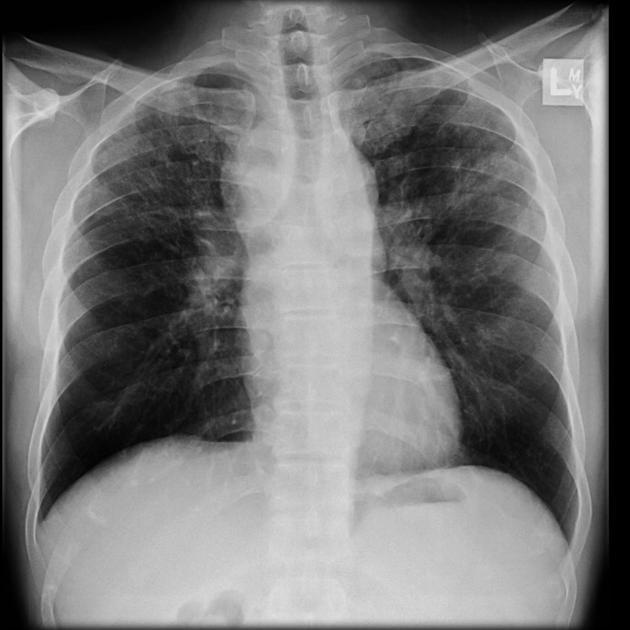

(sarcoidosis)

What is this?

Chronic bilateral airspace opacification is a subset of the differential diagnosis for airspace opacification. a useful framework is as follows:

inflammatory

sarcoidosis ( is an inflammatory disease that affects multiple organs in the body, but mostly the lungs and lymph glands)–Wegener’s granulomatosis ( is a rare disorder in which blood vessels become inflamed.)–eosinophilic pneumonia--cryptogenic organizing pneumonia( formerly bronchiolitis obliterans organizing pneumonia (BOOP))–polyarteritis nodosa is a systemic vasculitis of small- or medium-sized muscular arteries, typically involving renal and visceral vessels but sparing the pulmonary circulation)(PAN)–Churg-Strauss syndrome (s an autoimmune condition that causes inflammation of small and medium-sized blood vessels (vasculitis) in persons with a history of airway allergic hypersensitivity (atopy))